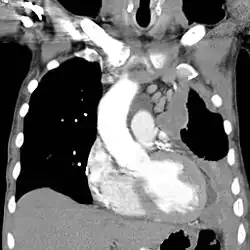

| CT scan showing a left sided mesothelioma with an enlarged mediastinal lymph node | |